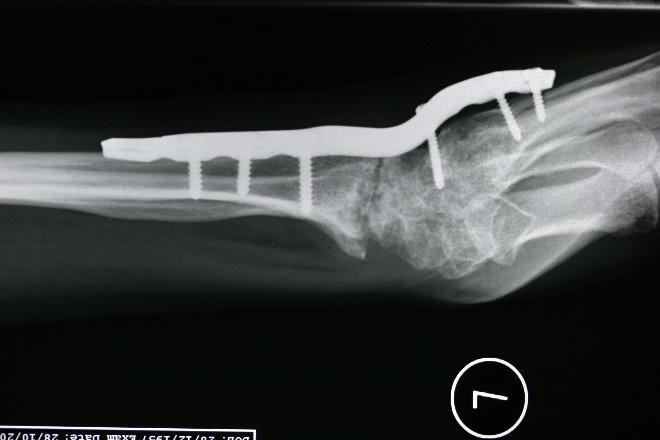

Skafolunat ekleminin ayrıldığını gösteren bileğin stresli görünümü

Aşağıda gösterildiği gibi, instabiliteyi sabitlemek için volar ve dorsal ligamanın skafolunatını tendon grefti ile yeniden yapılandırmak genellikle tercih edilen prosedürdür.